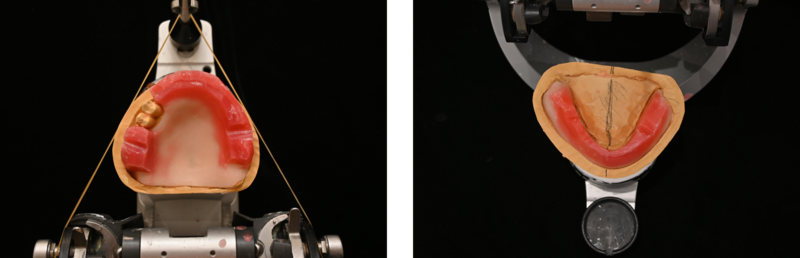

入れ歯の歯を並べました。

噛み合わせをとったら、咬合器という装置に模型を装着します。患者さまのお口を患者さまの次に1番知っているため、私が自分で行います。

写真で見てみると噛む面がだいぶ曲がっています。そして、向かって左の奥歯は交叉咬合に歯を排列しました。

上の天然の歯が残っている箇所がそのまま下にスッと噛んでくるとちょうど下の歯の真ん中に来てしまい、正常には噛まないわけです。下の歯をどこに並べれば上手く噛めるかということを考えながら歯を並べます。

試行錯誤して並べた状態が写真になります。並べてみて本当にこの並べ方で問題ないのか、確認が必要です。

出来上がった入れ歯です。向かって左側は、交叉咬合排列で上と下の入れ歯を噛み合わせました。向かって右側は、通常の排列で上下を噛ませました。